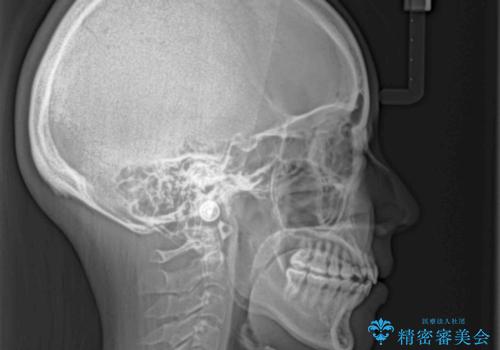

カリエールディスタライザーを併用したことで、確実かつ短期間で治療を終えることができました。